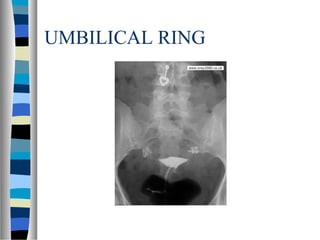

UMBILICAL RING